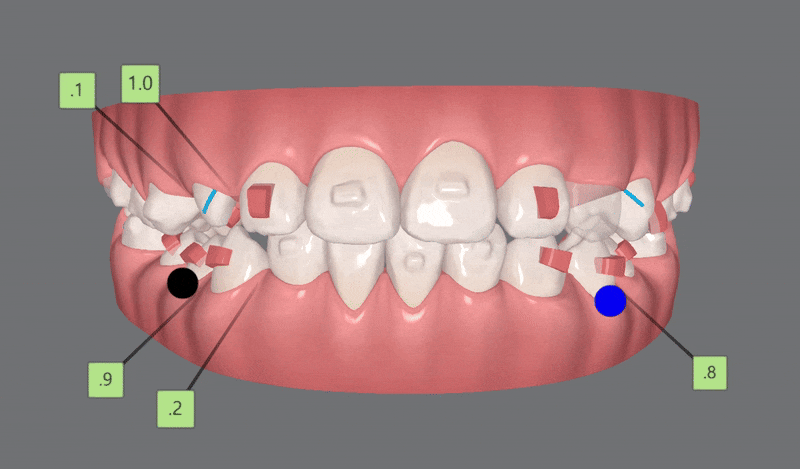

2nd Clincheck(21개)

두번째 클린체크에서는

21개의 장치로 진행해드렸는데요.

기존 어태치먼트에 추가로 어태치를 부착해

치아이동을 원활하게 도와주었습니다.